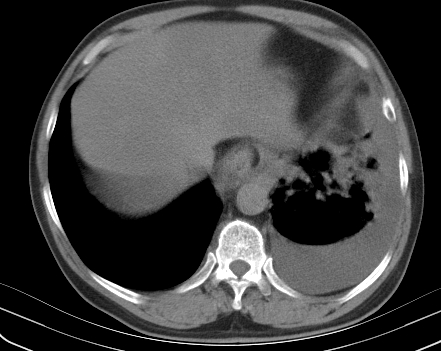

以下是引用老爱克斯新网客在2008-7-31 6:30:00的发言:[br]左肺上叶大片状病灶,左肺上叶支气管狭窄呈鼠尾状,左肺门增大,纵隔内见肿大淋巴结,左侧胸腔积液,余肺清晰。左肺中心型肺癌淋巴结转移,

以下是引用zjzjr在2008-7-31 8:45:00的发言:[br]考虑左侧中心性肺癌伴阻塞性肺炎,左肺上叶肺不张,纵隔淋巴结转移;左侧胸腔积液。建议行纤支镜检查。

以下是引用zjb在2008-7-31 6:32:00的发言:[br]左侧中心性肺癌 阻塞性肺炎 肺不张 胸腔积液 建议气管镜

以下是引用sdzyy在2008-7-31 8:47:00的发言:[br]病灶较治疗前有所进展,胸水增多, 左侧中心性肺癌 并 阻塞性肺炎 肺不张 胸腔积液 可能性大; 建议气管镜检查。 [br] [br]